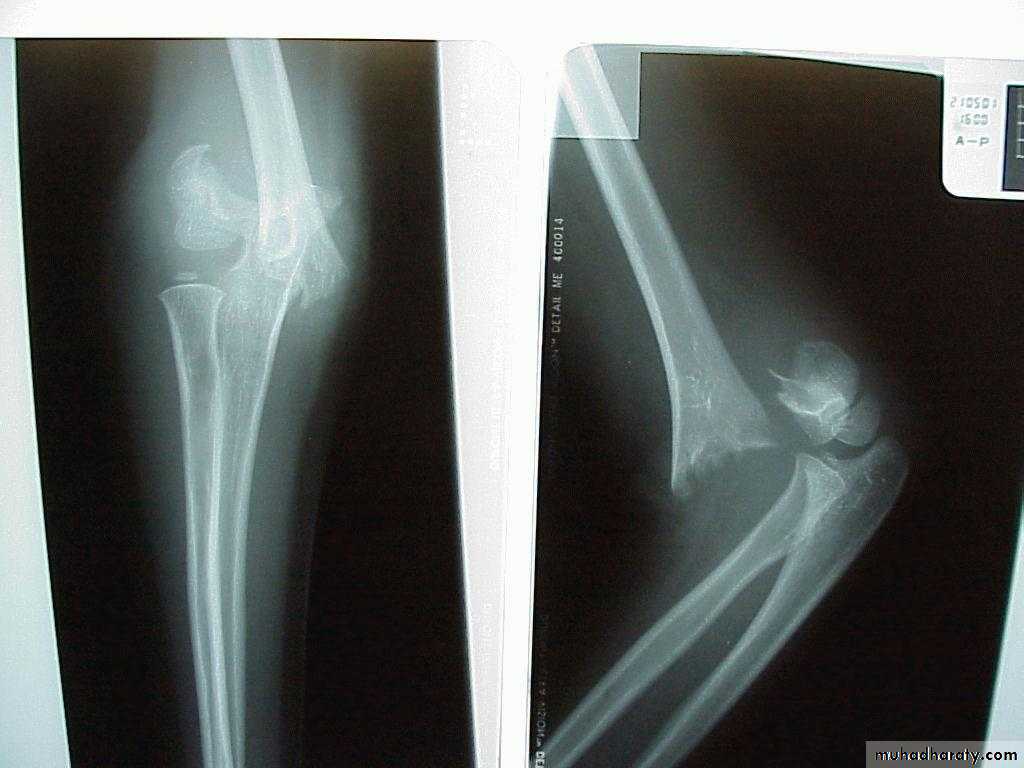

This fracture

was irreducibleby closed

manipulation.

Injury film